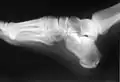

Squelette du pied, surface médiale.

Squelette du pied, surface latérale.